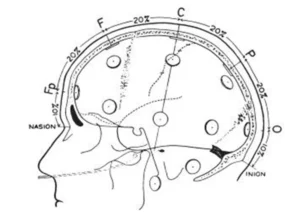

Technique of Measurement

The measurement technique is based on standard landmarks of the skull. Namely, the nasion, inion, and the left and right preauricular points. The preauricular points are felt as depressions at the root of the zygoma, just anterior to the tragus.

The first measurement is in the anterior-posterior plane through the vertex, taken from the nasion to the inion. This measurement is divided into 5 separate areas (see fig.1).

The first mark is placed at 10% of the total measurement and labeled Fp. The second, third, fourth and fifth marks are placed at 20% intervals of the total measurement and labeled F, C, P, and O. Note that the O mark would be located at 10% of the measurement above the inion. The expression Fp, F, C, P and O represent the fronto polar, frontal, central, parietal and occipital areas, respectively.

Lateral measurement of the central coronal plane strats at the left preauricular point thrugh the C vertex mark to the right preauricular point (fig.2). A mark is placed at 10% of this measurement over the preauricular points and labeled T.

The expression T represents the temporal area. Marks are then located at 20% of the lateral measurement and labeled left and right C, and the C vertex location is crossed.

A circumferential measurement (fig.3) is then taken over the temporal lobes from the midline Fp position to the midline O position.

A mark is made at 10% of this measurement indicating the left or right Fp electrode position. Marks are then made at 20% of the measurement and are labeled inferior frontal, mid-temporal, and posterior temporal and left or right occipital (note that the mid-temporal electrode positions are crossed). The remaining 10% measurement from the left and right occipital marks would be the midline = position. Variations of this measurement have been described by Harner and Sannit (1974)

Fig.1 Lateral view oof skull to show methods of measurement from nasion to inion at the midline. Fp is frontal pole position, F is the frontal line of electrodes, C is the central line of electrodes, P is the parietal line of electrodes and O is the occipital line. Percentages indicated represent proportions of the measured distance from the nasion to the inion. Note that the central line is 50% of this distance. The frontal pole and occipital electrodes are 10% from the nasion and inion, respectively. Twice this distance, or 20% separates the other lines of electrodes